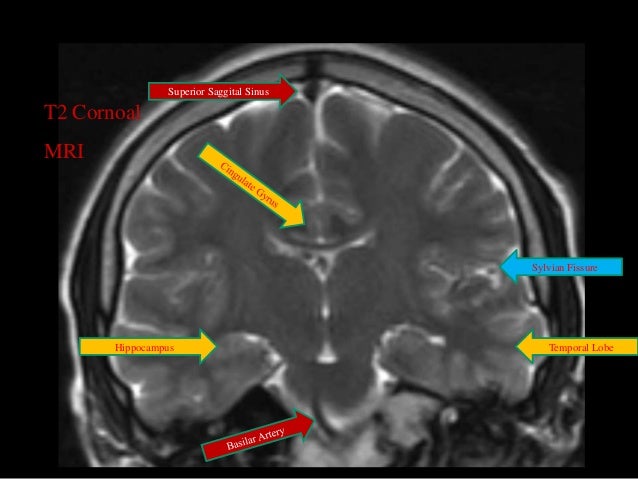

Brain Mri Anatomy

Brain mri anatomy self assessment presents animated interaction quizzes for students to practice identifying mri structures per brain transverse level. Zapawa and anthony l. The anatomy of the brain is studied by means of axial coronal and sagittal views.

Frontal lobe parietal lobe temporal lobe. Axial view coronal view. Normal anatomy in 3 d with mripet javascript atlas of normal structure and blood flow.